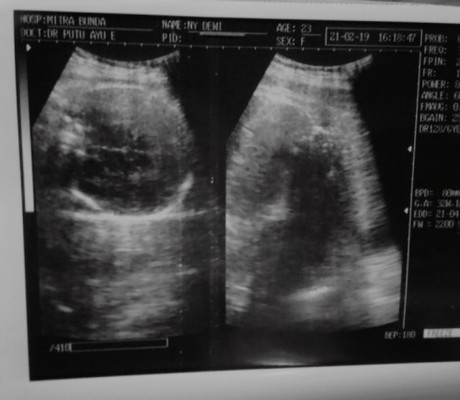

Assalamualaikum bunda, sharing dong ttg bunda yg pernah hamil diusia kandungan 34 minggu di usg posisi masih sungsang. Pertanyaan saya apakah bayi bunda masih bisa muter ke posisi yg tepat kemudian lahir normal? Kasih tipsnya juga biar posisi kepalanya ga sungsang lagi gimana ya? Adakah cara yg paling efektif? 😢😢 Malang, 04/03/21 #seriusnanya #firstbaby